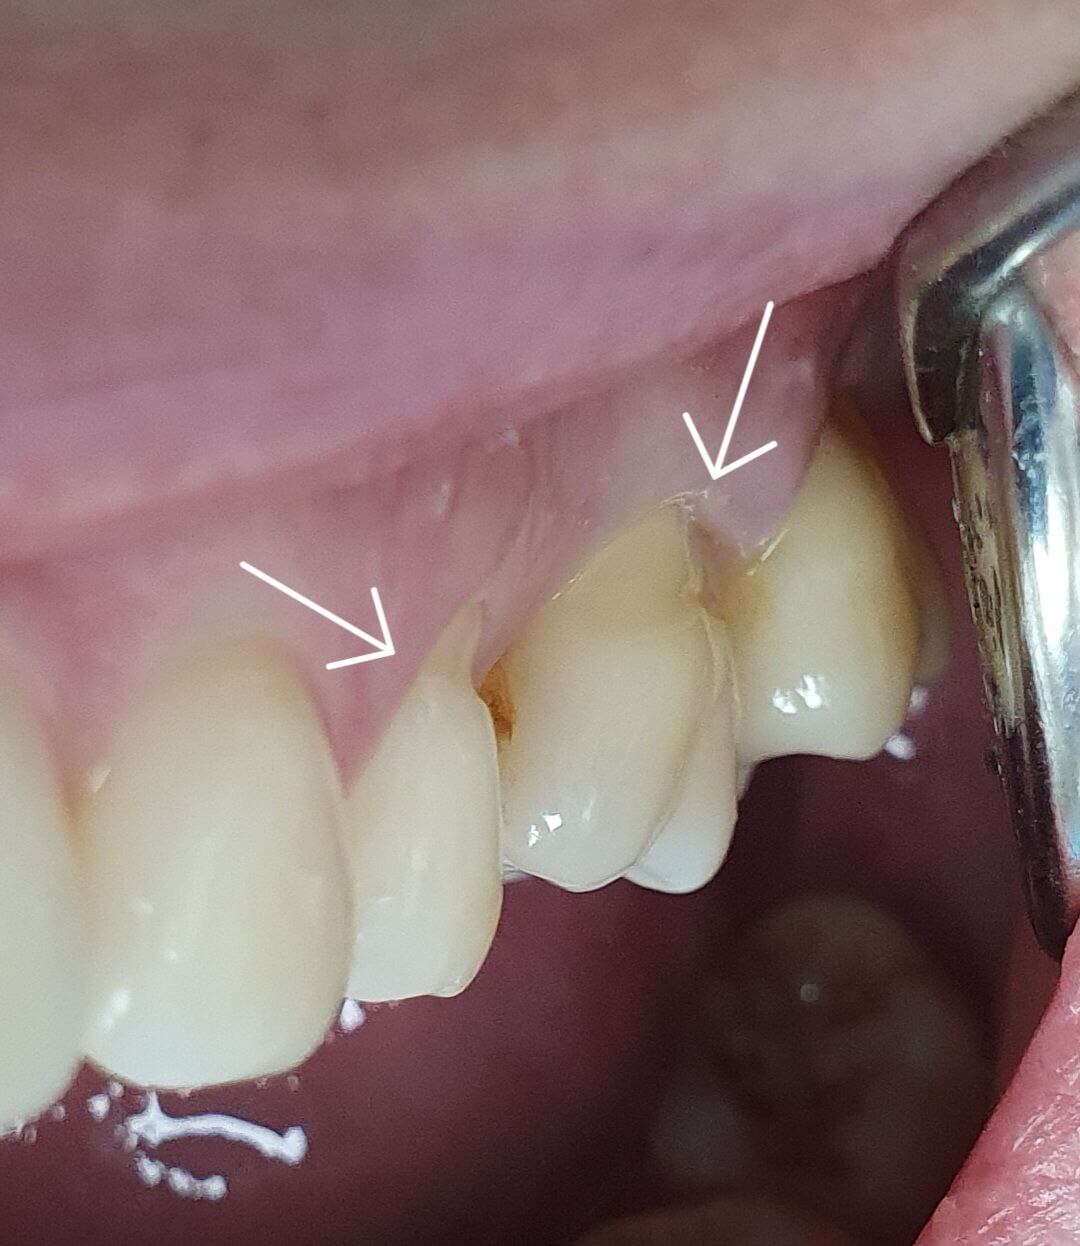

Придесневой дефект. Выявление причин и восстановление обязательно.